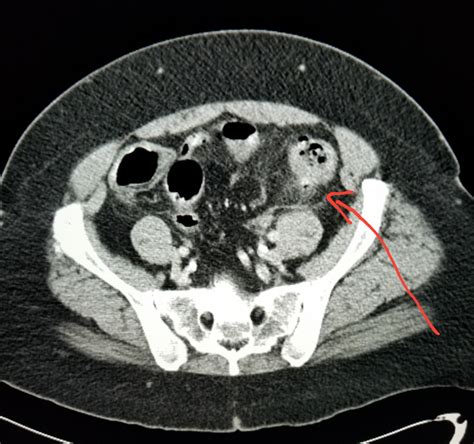

Diverticulitis is a painful condition that occurs when small pouches in the colon, known as diverticula, become inflamed or infected. When a patient presents with symptoms such as severe abdominal pain, fever, and changes in bowel habits, physicians must act quickly to make an accurate diagnosis. Among the various diagnostic tools available in modern medicine, a CT scan for diverticulitis is considered the gold standard. Its ability to provide detailed, cross-sectional images of the abdomen allows healthcare providers to confirm the presence of inflammation, assess the severity of the condition, and rule out other potential causes of abdominal distress.

Once the scan is completed, a radiologist will interpret the images and generate a report. If the scan confirms a diagnosis of diverticulitis, the radiologist will often grade the severity of the disease. This grading system is crucial for determining the appropriate course of treatment. The results of your CT scan for diverticulitis will likely focus on several key indicators:

• Wall Thickening: The degree to which the colon wall has thickened due to inflammation.

• Fat Stranding: A hazy appearance in the fat surrounding the colon, which is a classic sign of localized inflammation.

• Presence of Abscesses: Whether there are pockets of pus that may require drainage or specific antibiotic therapy.

• Free Air: A critical finding that may indicate a perforation, which is a medical emergency requiring immediate surgical consultation.